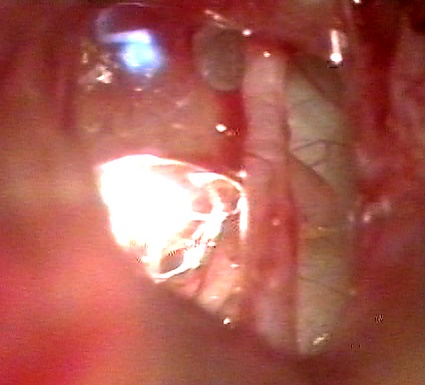

Нередко, даже после успешно проведённой операции экстракции катаракты, врачи встречаются с таким осложнением, как уплотнение задней капсулы хрусталика или вторичной катарактой. Для восстановления прозрачности оптических сред глаза применяется метод лазерной дисции (рассечения) задней капсулы хрусталика, отличающийся высокой эффективностью в сочетании с малоинвазивностью.

Процедура лазерной дисцизии задней капсулы хрусталика проводится амбулаторно, на фоне местной анестезии, она абсолютно безболезненна. Лазерные лучи избирательно локально воздействуют на ткани задней капсулы хрусталика, удаляя мутную часть капсулы. Благодаря такому воздействию, удаётся восстановить прозрачность оптических сред глаза. Большинство больных отмечают мгновенное улучшение зрения непосредственно после операции.